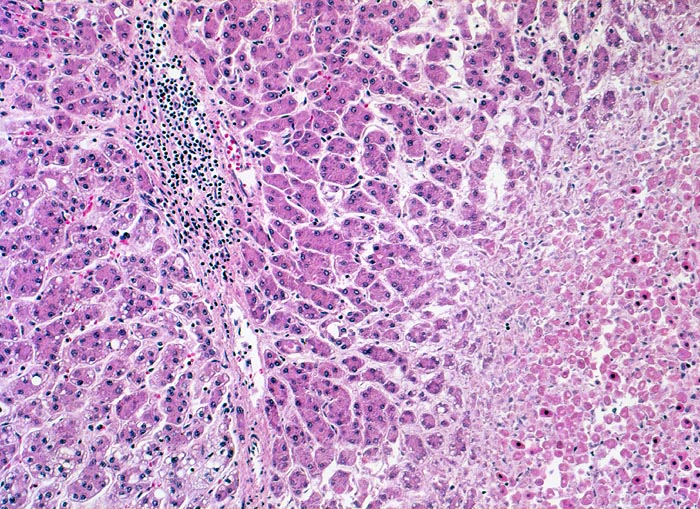

hepatozelluläres Karzinom mit Tumornekrosen

Die Tumortrabekel sind in diesem Tumorabschnitt lediglich zwei Zellen breit. Lediglich die minimalen Zellatypien (verminderte Menge basophiles Zytoplasma, geringe Kernatypien) ermöglichen die Unterscheidung von einem Leberzelladenom. Das Tumorgewebe enthält fibröse entzündlich infiltrierte Septen mit Gefässen. Portalfelder mit Gallengängen fehlen. Das nekrotische Tumorgewebe ist heller gefärbt.

Patient mit bekannter chronischer Hepatitis C. Bei einer sonographischen Kontrolluntersuchung wird ein 1cm grosser Knoten entdeckt. Das Alpha-Fetoprotein im Serum ist nicht erhöht.